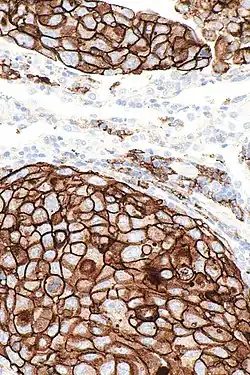

PD-L1 is shown to be highly expressed in a variety of malignancies, particularly lung cancer. In order to anticipate the effectiveness of gene therapy or systemic immunotherapy in blocking the PD-1 and PD-L1 checkpoints, PD-L1 might be employed as a prognostic marker and a target for anti-cancer immunity.[28] i.e. upregulation of PD-L1 may allow cancers to evade the host immune system. For example, an analysis of 196 tumor specimens from patients with renal cell carcinoma found that high tumor expression of PD-L1 was associated with increased tumor aggressiveness and a 4.5-fold increased risk of death.[29] In a model of A20 leukemia cells injected into F1 mice, NK cells killed target tumor cells with similar efficiency regardless of PD-L1 expression, whereas PD-L1 expression on A20 tumor cells conferred significant tumor protection against rejection by CD8 T cells confirming the role of the co-inhibitory receptor PD-1 in the modulation of their cytotoxic activity.[30]

Many PD-L1 inhibitors are in development as immuno-oncology therapies and are showing good results in clinical trials.[31] Clinically available examples include durvalumab, atezolizumab and avelumab.[32] In normal tissue, feedback between transcription factors like STAT3 and NF-κB restricts the immune response to protect host tissue and limit inflammation. In cancer, loss of feedback restriction between transcription factors can lead to increased local PD-L1 expression, which could limit the effectiveness of systemic treatment with agents targeting PD-L1.[33] CAR-T[34] and NK cells[35] targeting PD-L1 are being evaluated for treating cancer. pSTAT-1 and PDL-1 expressions also strongly correlate in prostate cancer.[36]